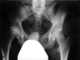

Avascular necrosis of femoral head

Avascular necrosis (AVN), also called osteonecrosis or bone infarction, is death of bone tissue due to interruption of the blood supply. Early on, there may be no symptoms. [Source: Wikipedia ]